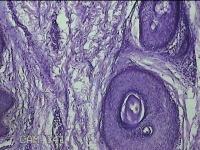

右腋下结节

性别

男

年龄

37岁

临床诊断

腋窝乳糜囊肿

一般病史

发现右腋下结节1年余,近日出现局部红肿及疼痛。

标本名称

大体所见

灰白暗红色组织2.7x1.8x0.8cm一块,表面带梭形皮肤2.8x1.3cm,皮下见结节2.7x1.3cm一个,切开结节呈实性,切面灰白粉红色,质软。

图1